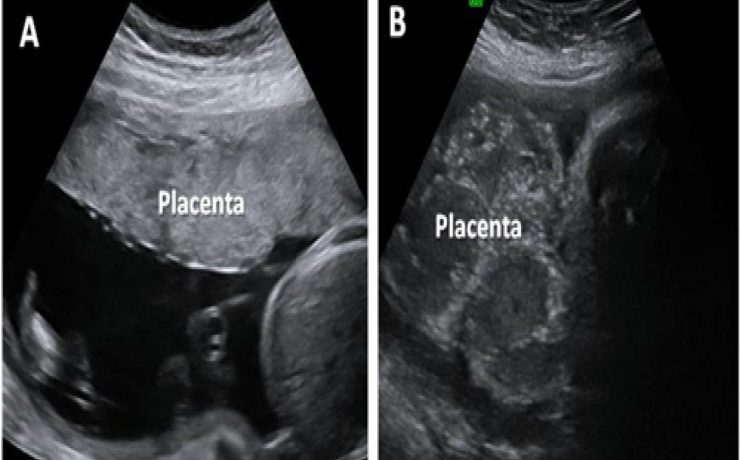

Durante el embarazo y la lactancia, la mama puede verse afectada por una variedad de trastornos únicos y específico, incluyendo trastornos benignos, relacionados con los cambios fisiológicos, inflamatorios, enfermedades infecciosas, papilomatosis juvenil y tumores benignos y malignos. Pacientes con carcinoma de mama asociada al embarazo presentan diagnóstico de neoplasias avanzadas y